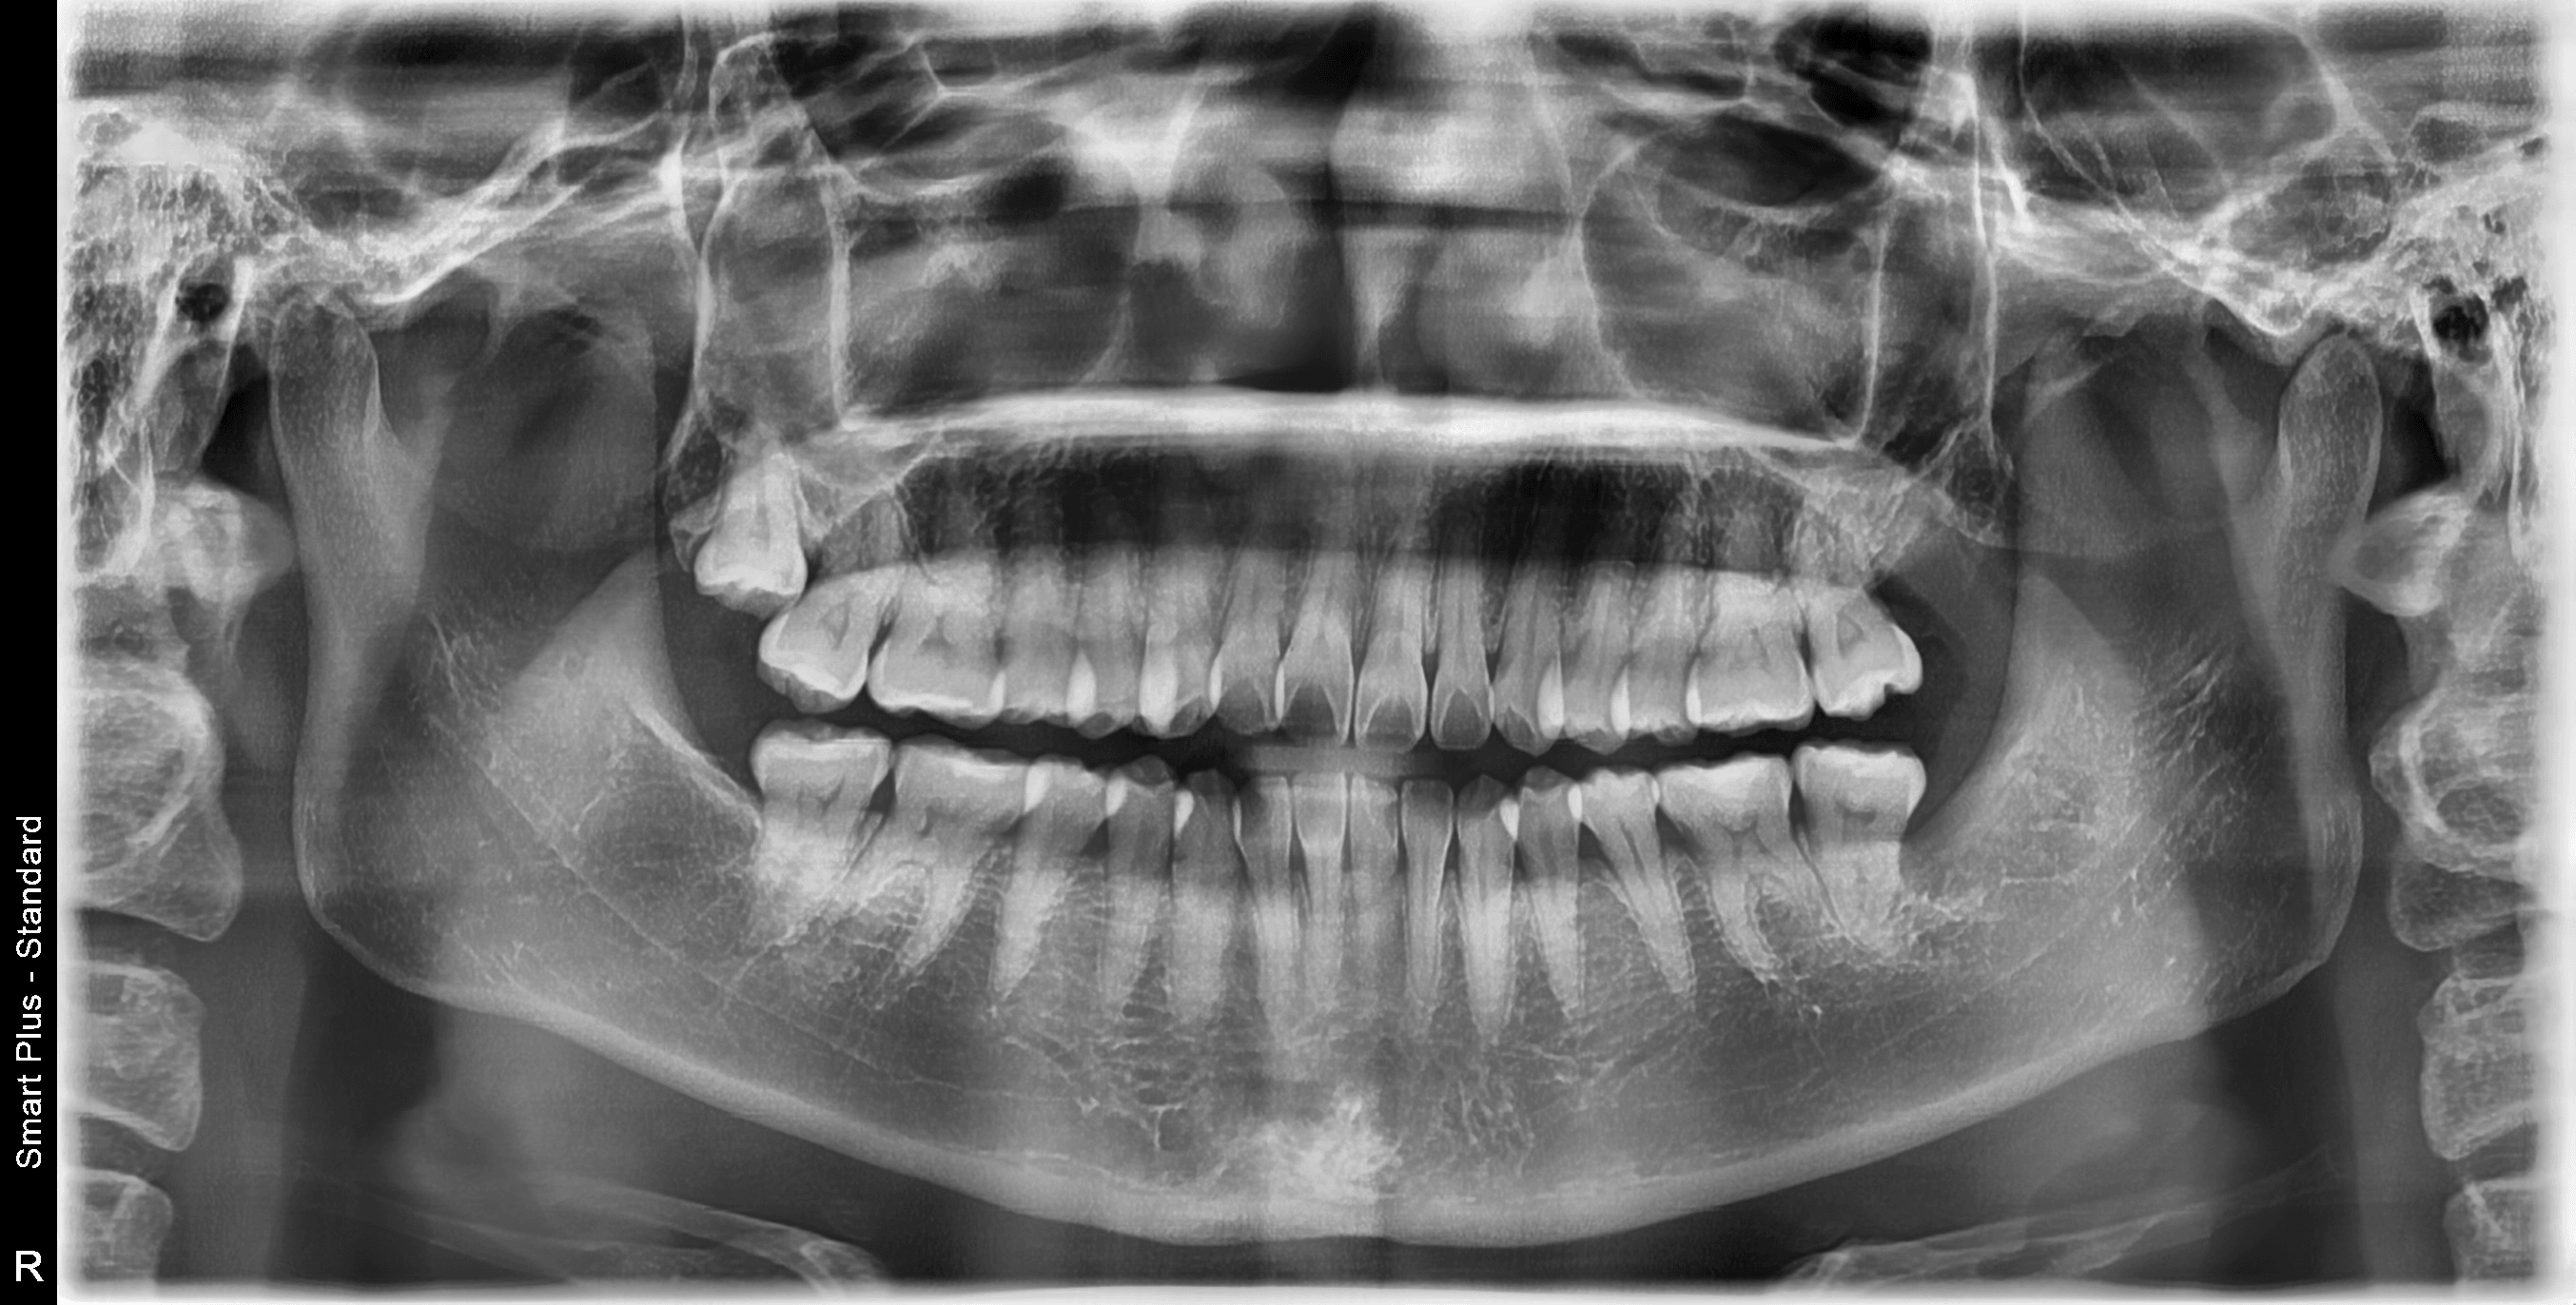

치료에 앞서 치과에서는 엑스레이나 CT 촬영을 통해 관절 뼈의 마모 상태를 확인하고, 입이 벌어지는 각도와 근육의 긴장도를 체크합니다. 다행히 턱관절 장애 환자의 약 90% 이상은 수술 없이 비수술적 보존 치료만으로도 증상이 호전됩니다. 대표적으로 염증을 가라앉히는 약물 요법, 근육을 이완시켜주는 적외선 및 저출력 레이저 물리치료, 그리고 턱 주변 근육의 긴장을 해소하는 보톡스 치료 등이 시행됩니다.